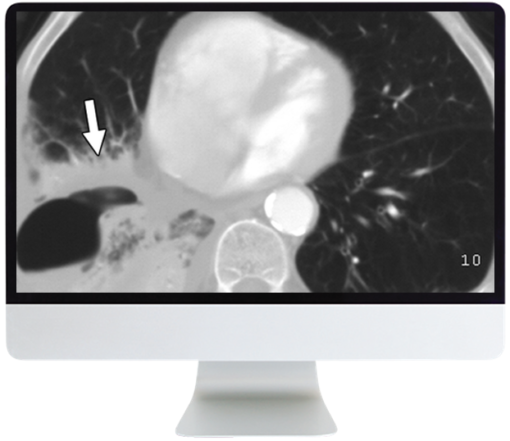

Module 3 — Chest

- Malignancies and Lung-RADS—Ahmed H. El-Sherief, MD

- Nodular Lung Disease: An Approach—Christopher Michael Walker, MD

- Diffuse Lung Disease—Maria Daniela Martin, MD

- Lymphatic Drainage of Thoracic Metastases—Christopher Michael Walker, MD

- Mediastinum—David Naeger, MD